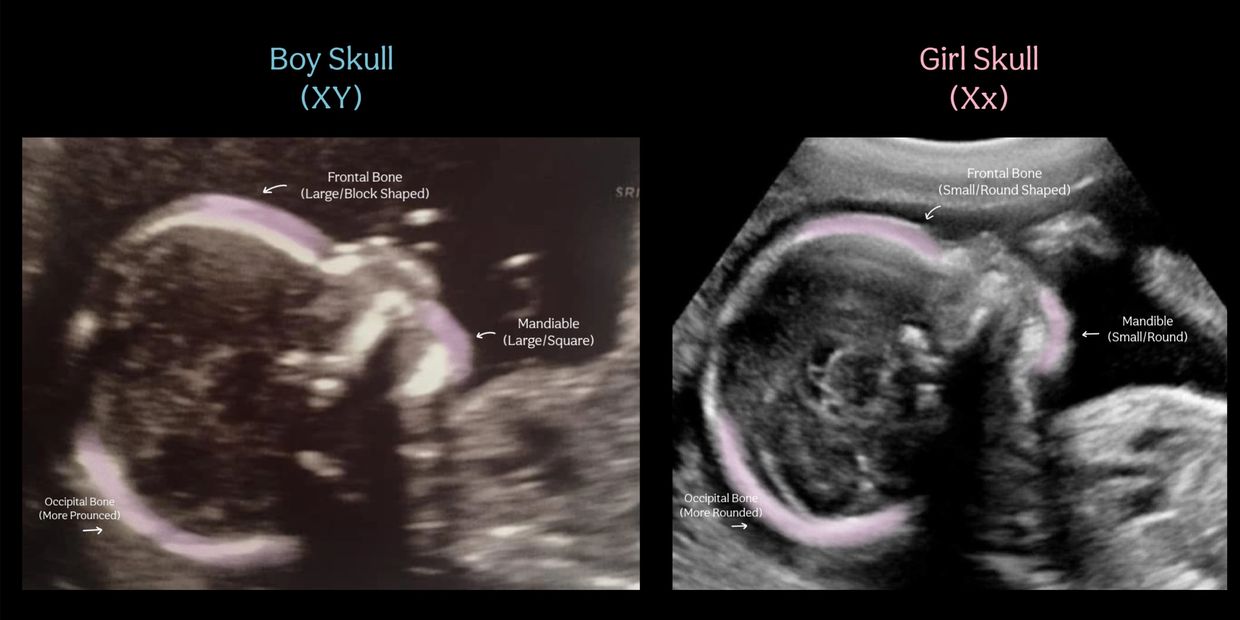

Skull theory uses markers such as the frontal, occiptal bone shape and appearance of the mandible to predict the gender of your baby.

According to this method male fetuses have larger/block like features and female fetuses have smaller rounded like features.

This theory has a much lower accuracy due to this your baby’s gender can be confirmed differently than we predict.